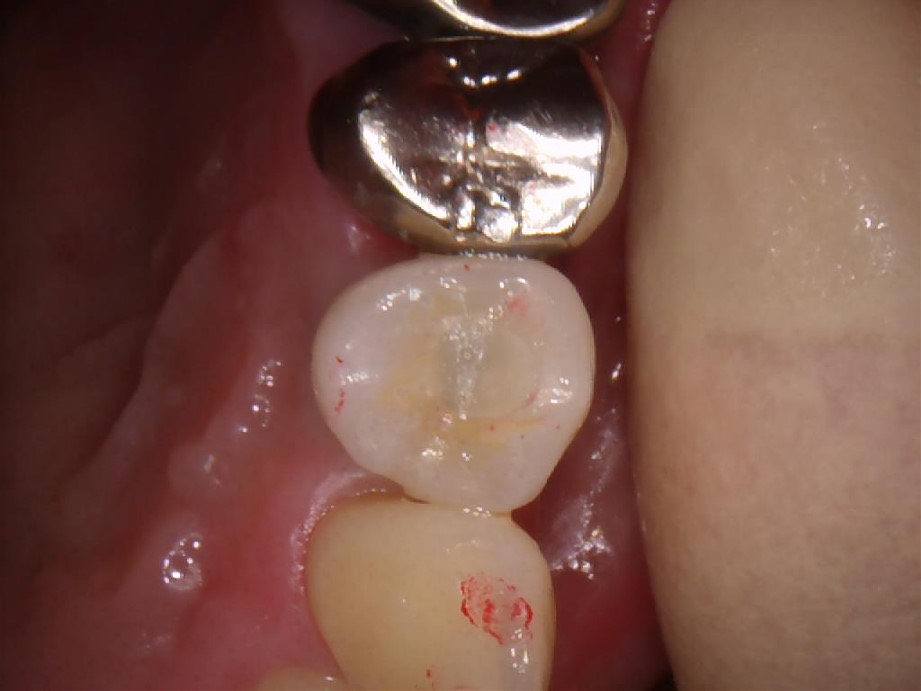

インプラントを入れた後の写真です。手術は15分程度で終わりました。術後も痛み止めを1回飲んだだけでその後は全く痛くなかったそうです。

横から見た写真です。